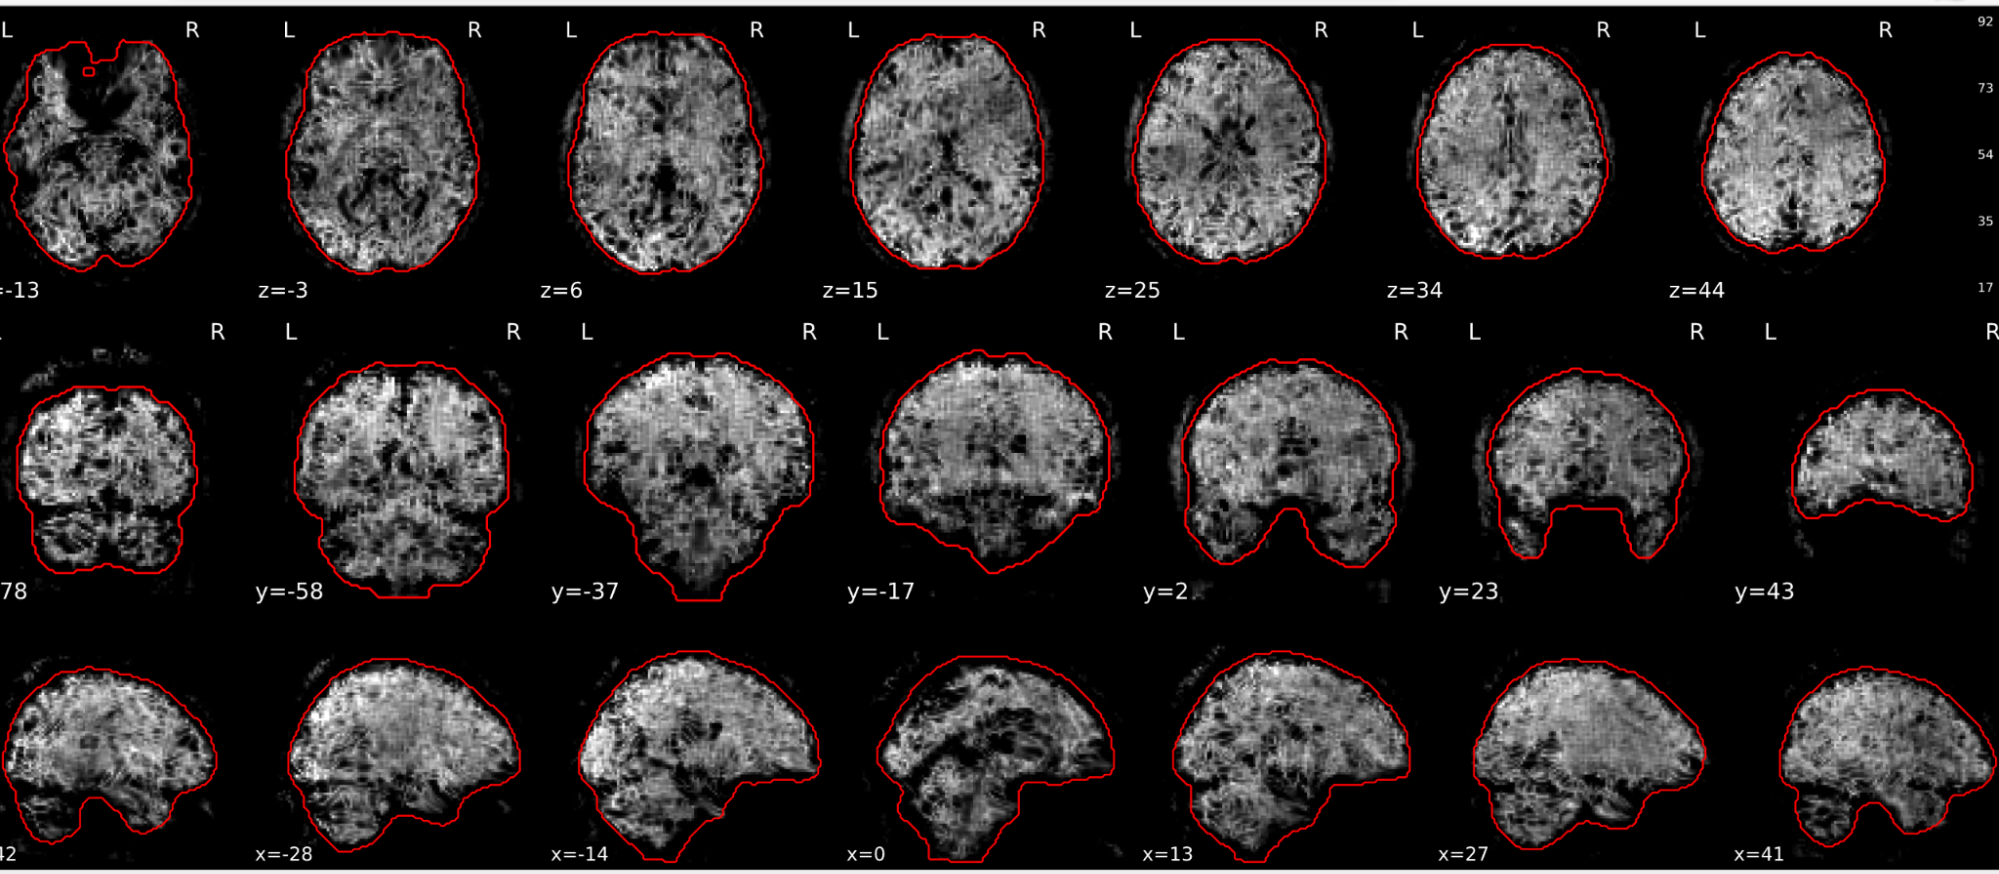

EPI tSNR

In the signal to noise ratio images of the resting state image the desired signal is compared to the amount of background noise. It is important to check all the views (sagittal, coronal, axial) because some artefacts (e.g., stripes) may be evident only in one particular view.

Example of a good subject

- Signal to noise is symmetrically distributed and there is no signal distortion

Example of a bad subject

- Asymmetry

- Potential signal distortion (might represent an artefact)

- Signal drop-out

- Stripes artefact

Clear large artefact (e.g., zebra stripes in example 1) are worth the exclusion of the subject. If you are unsure, check the other quality metrics for that subject to decide whether they should be excluded.

Summary

| good | bad |

|---|---|

| Symmetrical distribution of noise and signal | Asymmetry |

| No disruptions of the signal (no “black patches”) |

Potential signal disruptions (could be related to artefacts) |

| No stripes (sign of high motion) |

Signal drop |

| Stripe artefacts (“zebra” stripes due to motion) |